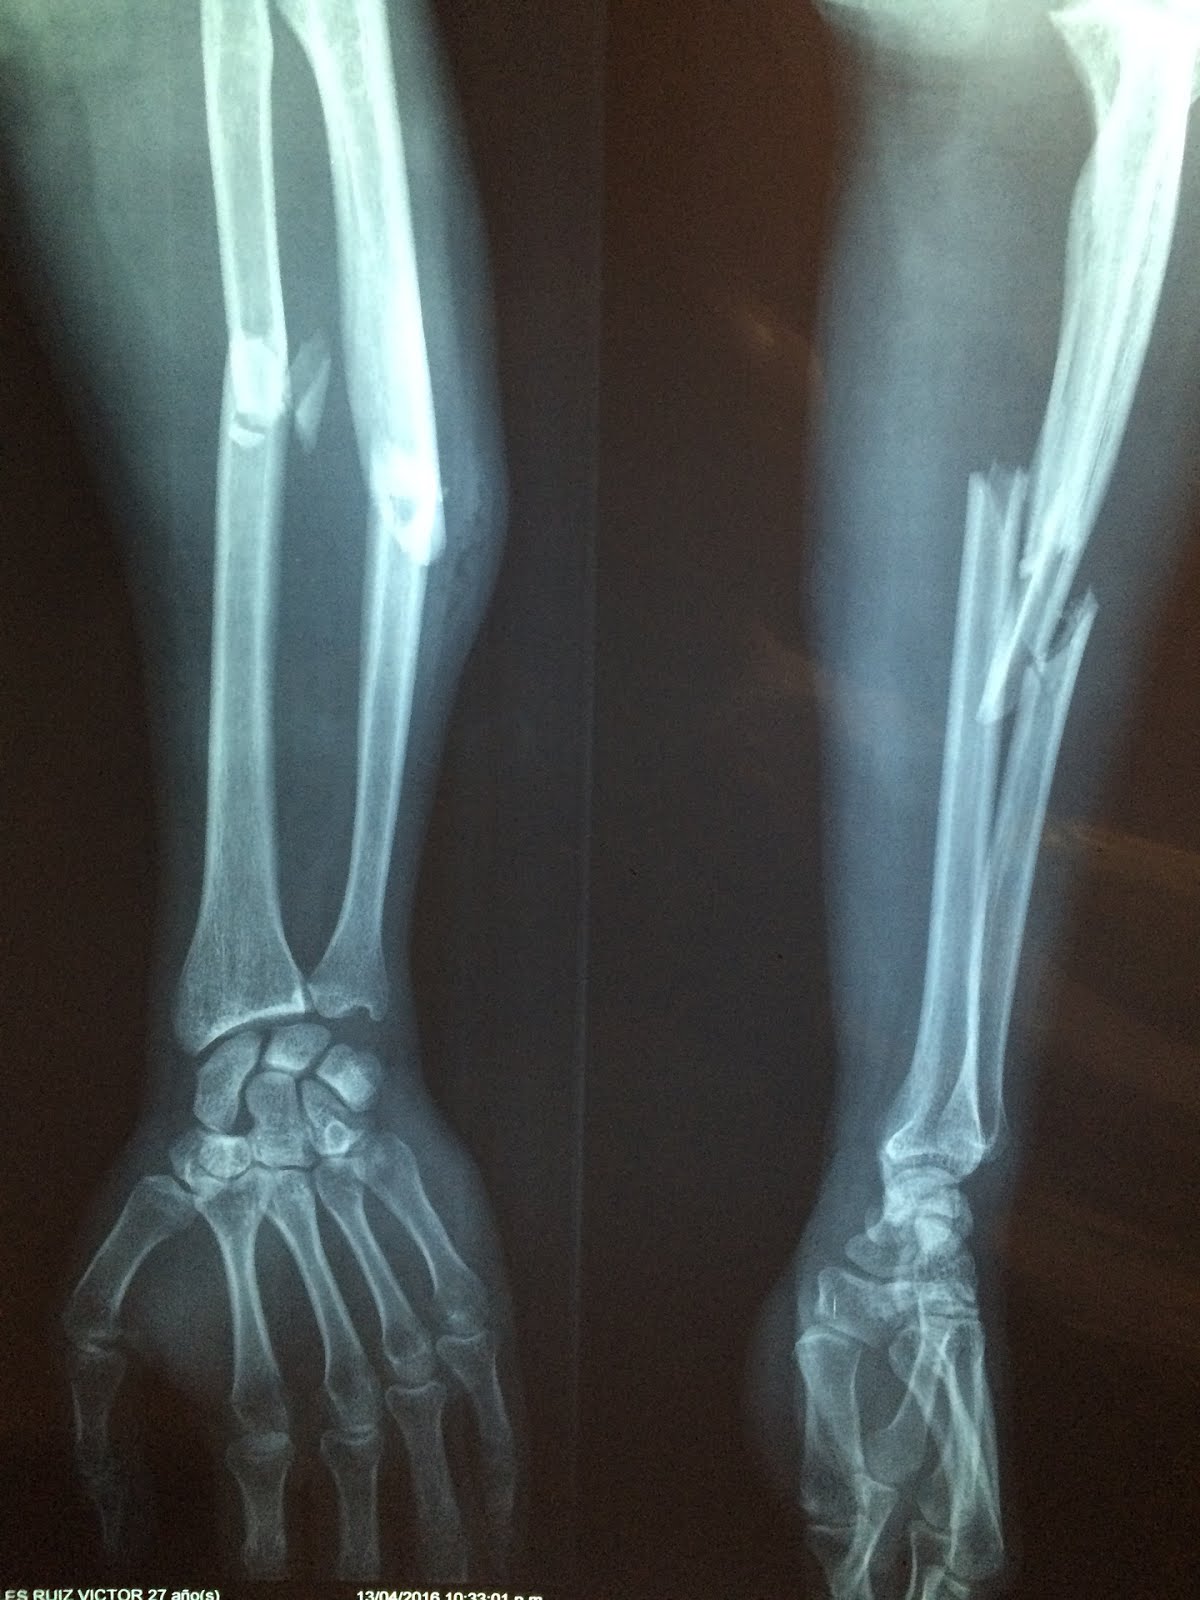

Distal Ulnar Fracture Activate Physiotherapy Can A Broken Bone Repair Itself provided that the conditions are right for the break to heal completely, a broken bone or fracture can actually repair itself. However, if the force is too great, bones can. explain how bone repairs itself after a fracture. bones are very flexible and can withstand a lot of physical force. bones may hurt while they heal;. Can A Broken Bone Repair Itself.